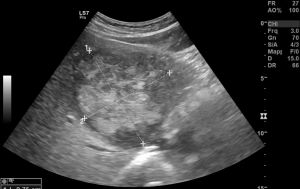

Ad oggi sono state identificate con l’ecografia addominale prevista dal protocollo, 9 neoplasie del parenchima epatico: 5 angiosarcomi (Fig. 1-4) (di cui 2 viventi) e 4 epatocarcinomi (Fig. 5-7) (di cui 1 vivente), successivamente sottoposte a studio TC e tutte confermate dalla diagnosi istologica.

Fig.2. Caso 1 di angiosarcoma epatico

Fig.3. Caso 2 di angiosarcoma epatico